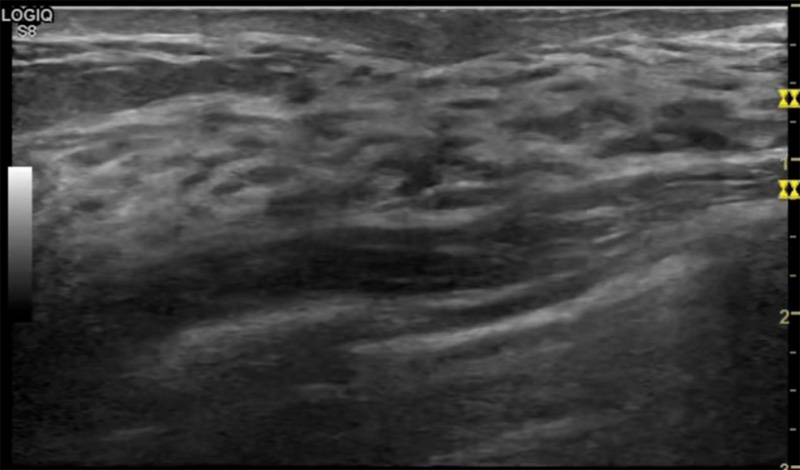

乳房脹痛,觸摸疼痛,手摸起來感覺有腫塊。這個是什么問題呢?醫(yī)生診斷一般是乳腺增生。那么在乳腺超聲設(shè)備檢查后,報告單卻顯示雙乳未見明顯占位性病變。乳腺增生是很多女性,特別是育齡期女性都有的經(jīng)歷、到底乳腺增生癥狀有哪些?會給我們帶來怎樣的影響呢?乳腺增生不是腫瘤跟炎癥。乳腺組織增生及退行性變跟內(nèi)分泌功能紊亂有關(guān)系。正常的生理改變。還有乳腺病,良性乳腺結(jié)構(gòu)不良等名稱。

乳腺增生有什么癥狀,病因?比較典型的就是乳房疼痛,特別是經(jīng)前癥狀比較重,經(jīng)后就有所緩解。有時候還能碰到乳房硬塊。根據(jù)經(jīng)期的變化而變化硬度大小都有變。乳腺在內(nèi)分泌激素,伴隨月經(jīng)周期有增生問題。內(nèi)分泌激素代謝失衡,雌激素水平增高,出現(xiàn)乳腺組織增生過度,增生組織不退的情況下,就會有乳腺增生癥狀。這個不會增加乳腺癌的風險。所以不用緊張的。不過乳腺癌的病人都會有乳腺增生。所以乳腺增長有沒癥狀,都需要進行常規(guī)的體檢。